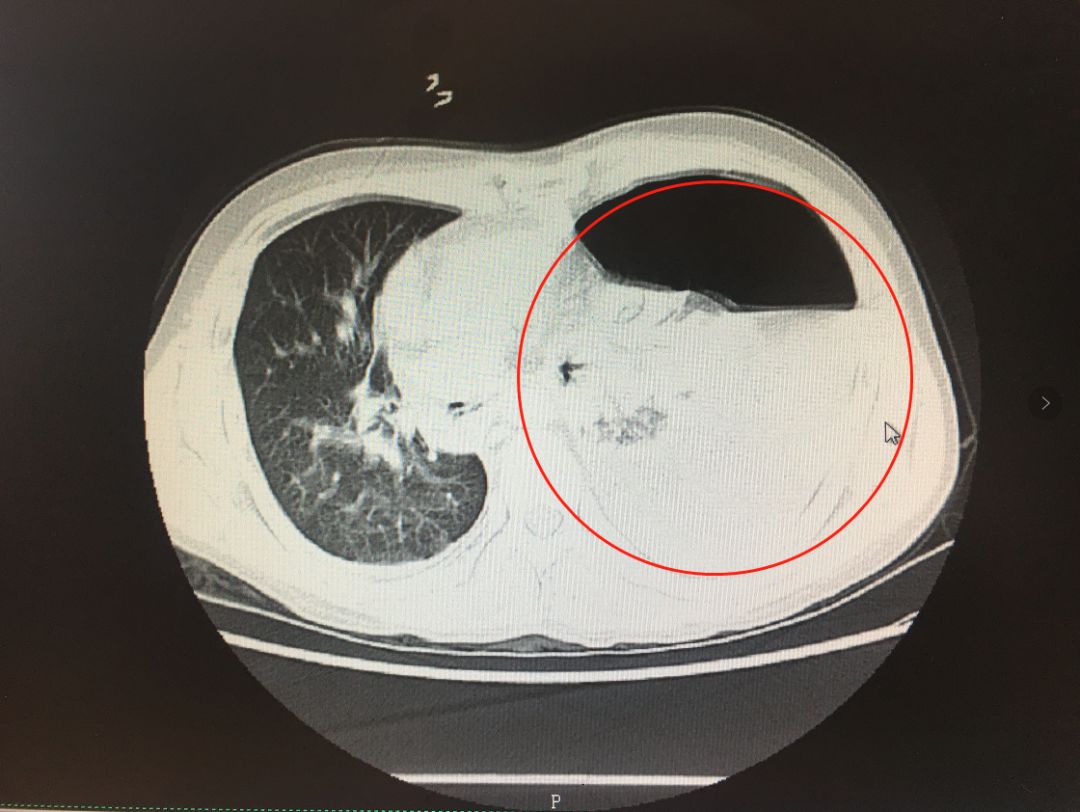

肺挫裂伤和肺血肿

左肺(影像中为右侧)毁损严重2019年,小夏因肺部不适来武汉市肺科医院